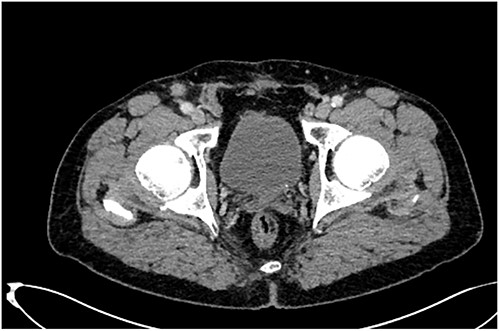

Furthermore, tumor marker levels, notably carcinoembryonic antigen (CEA) and cancer antigen 19-9 (CA 19-9), were normal. At a 2-year follow-up, the patient consulted for a right inguinal swelling. On physical examination, the abdomen was soft with no palpable mass and we found a right groin adenopathy measuring 4 cm. A biopsy was performed. Unexpectedly, it showed an adenocarcinoma metastasis in favor of a colonic origin. A CT scan was performed. There was no relapse of the disease. However, it revealed an enlarged right inguinal lymph node (Fig. 1). A resection of the inguinal lymph node was performed. Histological examination, after staining with hematoxylin and eosin, revealed a lymph node parenchyma massively invaded by a carcinomatous proliferation consisting essentially of glands and cribriform structures lined by a cylindrical coating with pseudostratified nuclei, the site of moderate to significant cytonuclear atypia with several mitoses (Fig. 2A). An immunohistochemical study showed a massive expression of cytokeratin 20 (Fig. 2B). This pathological examination led us to confirm the metastatic nature of the lymph node. As the positron emission tomography (PET) scan showed no other tumoral localizations, a multidisciplinary discussion ensued, culminating in the choice of chemotherapy for optimal pathological response.